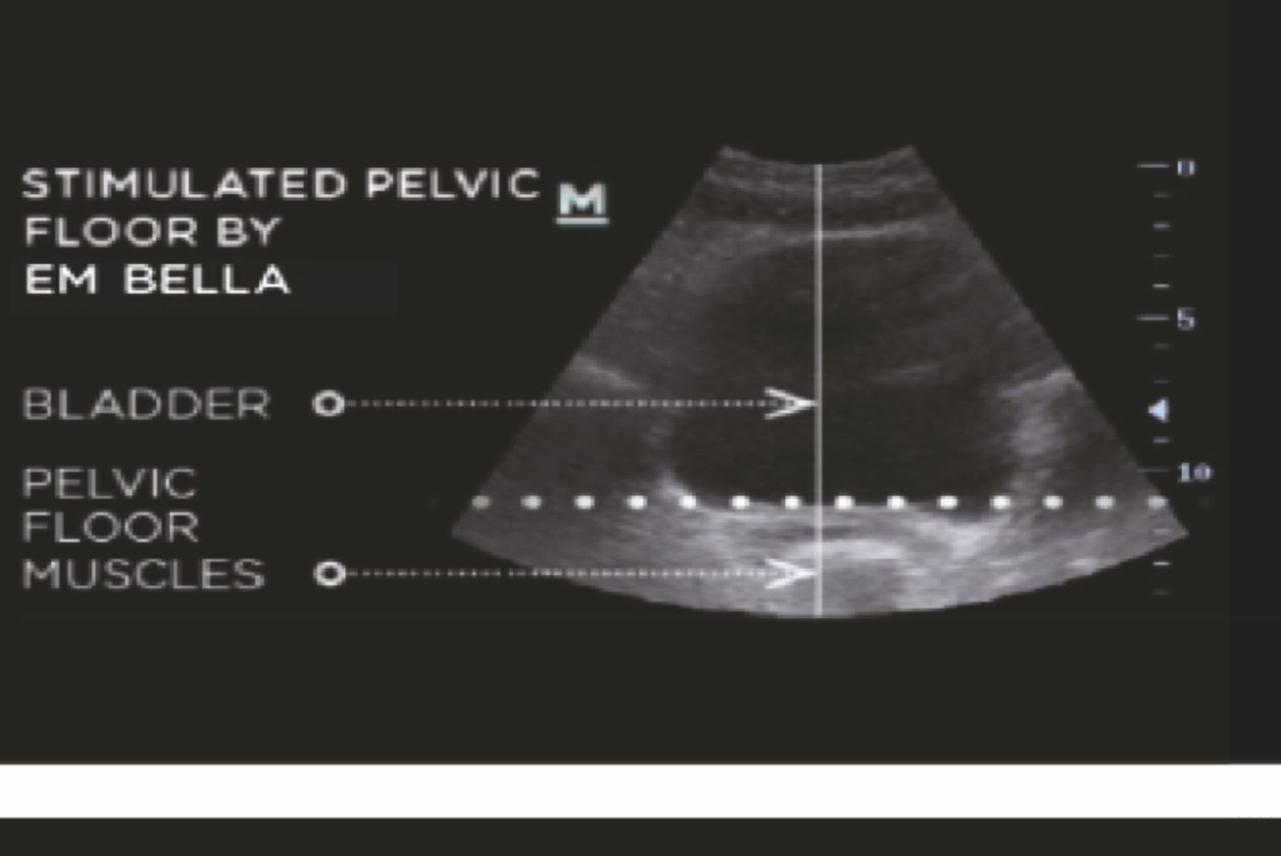

Bàn tập cơ sàn chậu kích thích hiệu quả các cơ sàn chậu với hàng ngàn con co thắt cơ mỗi lần điều trị.

SAU ĐIỀU TRỊ

Kích thích làm khỏe cơ sàn chậu, giúp lấy lại khả năng kiểm soát các cơ sàn chậu và bàng quang.